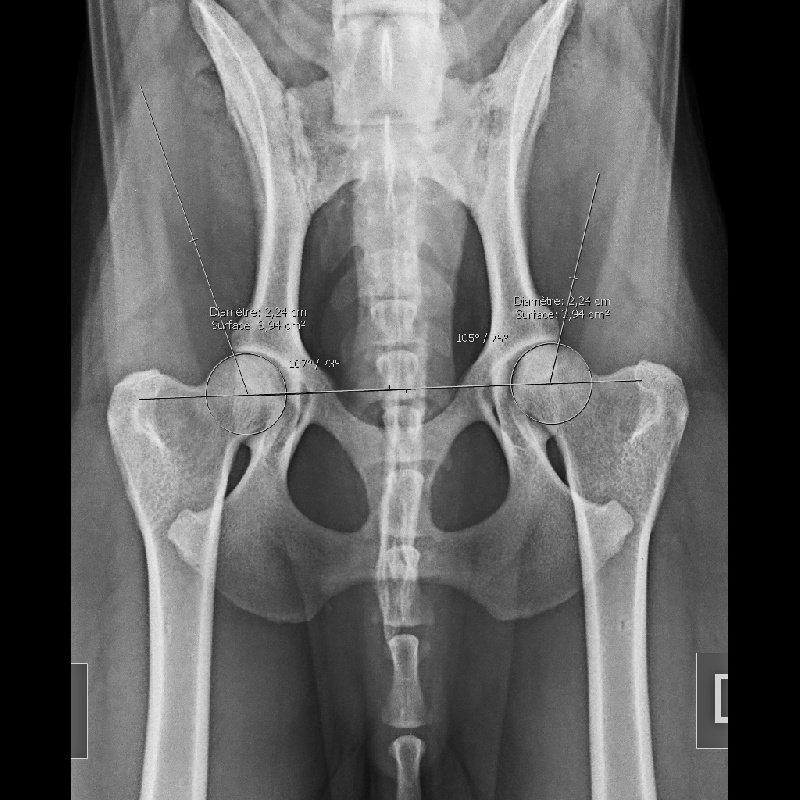

Chien Berger Belge Tsar de la Criniére Noire

tsar de la criniere noire mondio 2 et ring 2 point pour ring 3 pas de dysplasie et aucun signe d'arthrose

Dysplasie - AADysplasie des coudes - 0-Dys absTares Oculaires - exemptManque de dents - Aucune